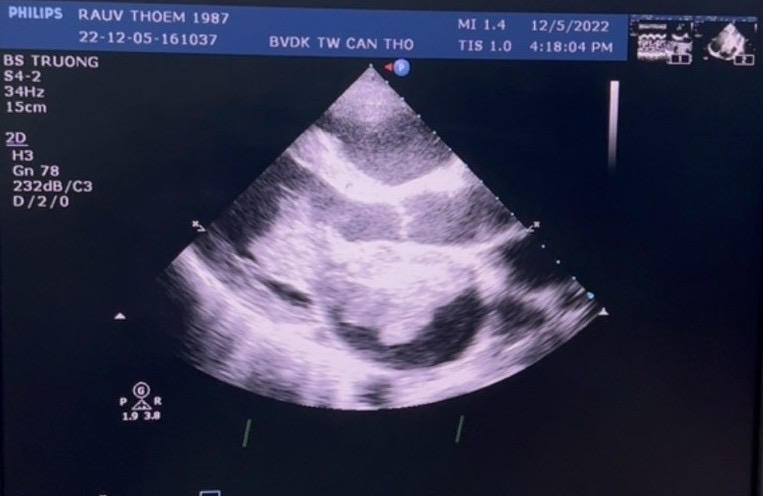

Bệnh nhân là anh R.T (35 tuổi, ngụ tỉnh Kampot, thuộc Vương quốc Campuchia), được chuyển đến bệnh viện trong tình trạng dương tính COVID-19, viêm phổi 2 bên, theo dõi u nhầy nhĩ trái. Sau điều trị COVID-19 ổn định, bệnh nhân được chuyển về khoa phẫu thuật tim điều trị tiếp. Các bác xác định nhĩ trái có 1 cấu trúc không đồng nhất gồm nhiều thùy, rất di động, cuống bám vách liên nhĩ, kích thước 70 x 52mm, nguy cơ vỡ rất cao ở hai cực của khối u, dọa lấp van 2 lá, hở van 3 lá 4/4, tăng áp lực động mạch phổi rất nặng 80mmHg.

Hình ảnh khối u nhầy trên siêu âm tim |

Kết quả hội chẩn xác đinh, bệnh nhân bị u nhầy nhĩ trái kích thước lớn dọa vỡ, dọa lấp van 2 lá, hở van 3 lá nặng, tăng áp động mạch phổi nặng, suy tim độ III, nhồi máu não cũ, hậu COVID-19.